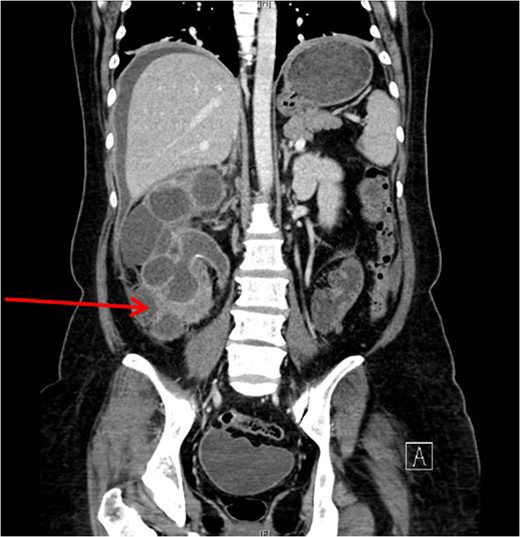

Xanthogranulomatous pyelonephritis (XGPN) is a rare form of chronic pyelonephritis with progressive loss of renal function. Commonly, obstructing urinary calculi are seen. It is difficult to differentiate between XGPN and malignancy in many cases, and the diagnosis is usually only confirmed post-operatively upon histopathological examination of the specimen. Surgical treatment is often the main treatment modality due to suspicion for malignancy. Here, we present a case of XGPN that presented with abdominal distension, which was eventually discovered to be due to a preperitoneal abscess.

She underwent insertion of a right percutaneous nephrostomy drain, percutaneous drainage of the anterior abdominal collection, as well as a percutaneous biopsy of the right renal soft tissue lesion. Urine cultures from the percutaneous nephrostomy grew Proteus mirabilis. Fluid cytology from the abdominal collection showed acute inflammatory cells. Biopsy of the renal lesion showed xanthogranulomatous inflammation.

Our patient had an atypical presentation with abdominal distension and presumed ascites, which was eventually revealed to be an anterior preperitoneal collection secondary to infection. Although the initial suspicion was that of a malignant process complicated by ascites, subsequent cytology and histopathological results showed that it was likely benign. In view of the non-functioning renal unit and significant abdominal collection, she underwent definitive surgery.

The most common urinary pathogen identified was Escherichiacoli [3], and common areas of involvement were the retroperitoneum and psoas muscle. In our patient, the retroperitoneal space was surprisingly not greatly involved, but rather it was the anterior preperitoneal space that had significant adhesions and inflammation. The pathogen identified from both nephrostomy and preperitoneal collection was P. mirabilis, showing that both pathologies were linked.